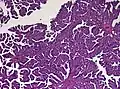

The tumor is neuroectodermal in origin and similar in structure to a normal choroid plexus. They may be created by epithelial cells of the choroid plexus. Papillary fronds lined by bland columnar epithelium are visible under the microscope. Normal absences include mitotic activity, nuclear pleomorphism, and necrosis.[10] Tumors have positive immunohistochemistry for cytokeratin, vimentin, podoplanin, and S-100.[11] Up to 20% of choroid plexus papilloma patients may test positive for glial fibrillary acidic protein (GFAP).[12] Studies have found that fourth ventricle cancers express more S100 than lateral ventricle tumors, and older patients (over 20 years) express more GFAP and transthyretin than younger patients.[13] Some individuals with choroid plexus papilloma have germline TP53 gene mutations, according to genetic analyses.[14] These cancers rarely exhibit nuclear p53 protein positivity. Aicardi syndrome, hypomelanosis of Ito, and 9p duplication are syndromic correlations of choroid plexus papilloma.

Micrograph of a choroid plexus papilloma. H&E stain. -